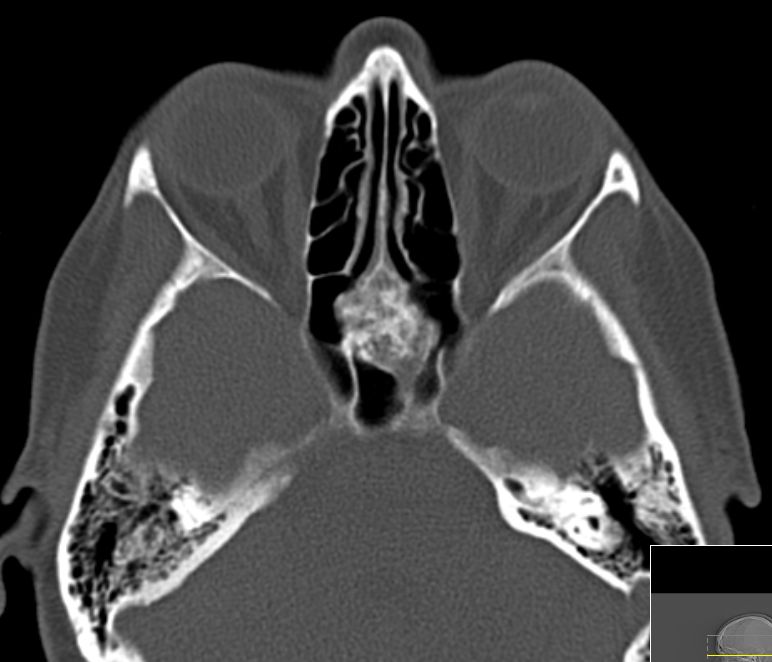

50-jährige Frau (I251), die vor 7 Jahre ein Mammakarzinom (rechts oben außen, T1c No Mo, invasiv NST hatte. Bisher metastasenfrei. Jetzt vor der Sella, in der linken Keilbeinhöhle eine z.T. verkalkte Raumforderung. 2 Jahre unverändert kontrolliert.